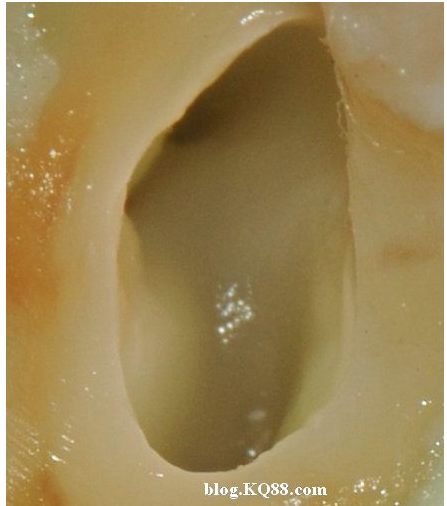

下邊這張圖可以看出氣泡明顯少了,說明次氯酸鈉的溶解速度變慢了。

棉球吸除2%的次氯酸鈉,可以看到牙髓明顯的被溶解掉一部分

換用5%左右的次氯酸鈉很快髓腔內(nèi)的牙髓溶解了